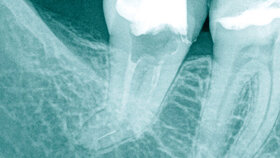

Der Nutzen für den Einsatz von Vergrößerungshilfen in der Endodontie ist weitgehend unbestritten. Während durch die Verwendung von Lupenbrillen bereits Verbesserungen in Diagnostik und Therapie zu erzielen sind, ermöglicht das Dentalmikroskop auch die Anwendung neuer minmalinvasiver Therapieverfahren. Michael Arnold, Dresden, gibt in seinem Beitrag einen Überblick über das Arbeiten mit Vergrößerungshilfen in der Endodontie.